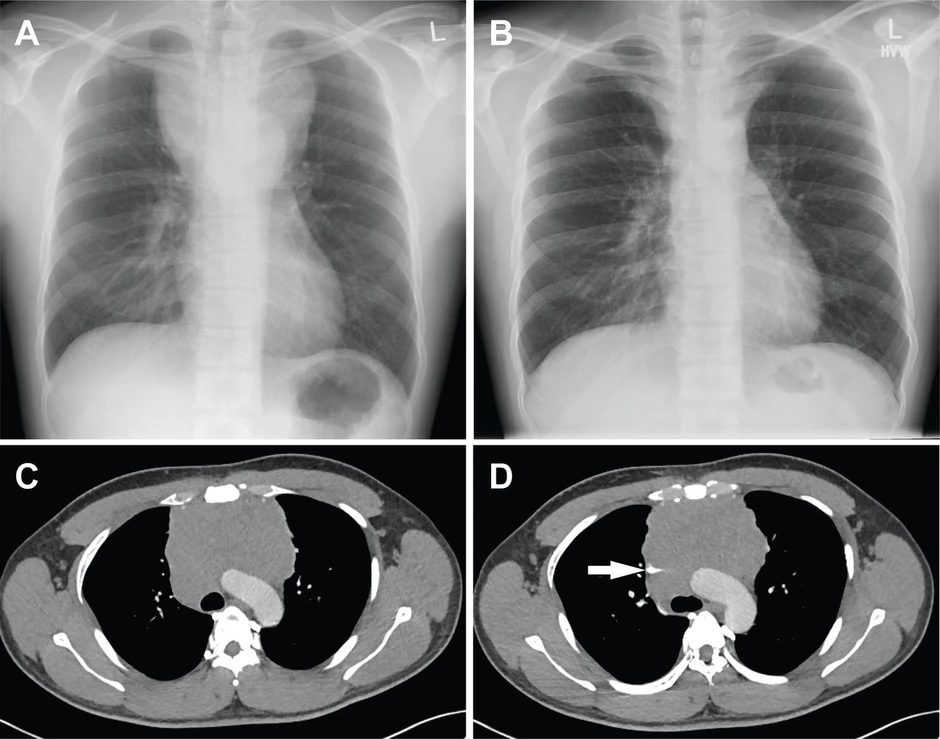

Prva stradaju pluća

Foto: BMJ Case Reports / Promo

Prva stradaju pluća (Foto: BMJ Case Reports / Promo)